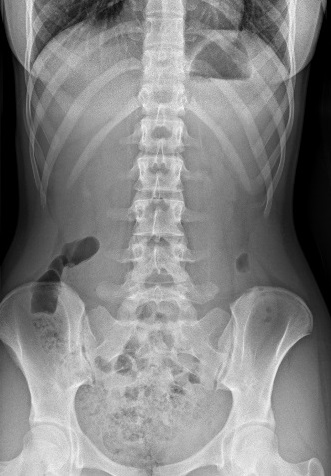

Para completar el estudio, se solicitaron radiografías simples anteroposterior y lateral de columna en bipedestación, encontrándose una megatranversa en L5, sin asimetría de extremidades inferiores ni desviaciones de la columna (Figura 1).

| Figura 1. Paciente de 14 años con dolor lumbar. Radiografía de columna anteroposterior en bidipestación con “sacralización” de L5 |